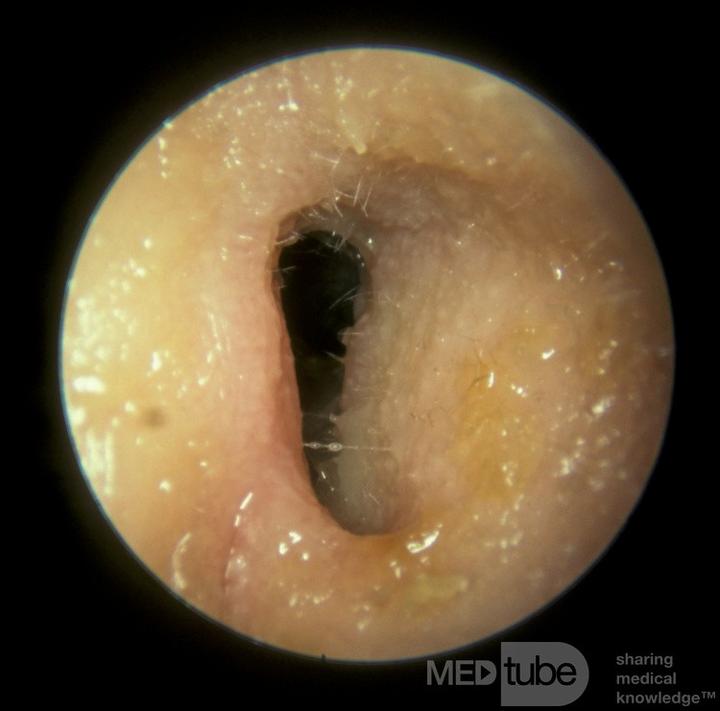

Wyróżniamy trzy rodzaje zapalenia ucha: zewnętrzne, środkowe i wewnętrzne. To ostatnie wydarza się niezwykle rzadko, natomiast zapalenie ucha środkowego występuje dość często, szczególnie u dzieci. Dlaczego tak się dzieje? Otóż ich trąbki Eustachiusza, czyli te fajne rurki łączące ucho z nosogardłem, są u maluchów krótsze i bardziej poziome. Właśnie dlatego wirusy z kataru mogą z łatwością przedostać się do ucha, co prowadzi do problemów. Pragnę jednak przypomnieć – zapalenie ucha nie przenosi się jak grypa; to wirusy i bakterie mogą być przekazywane. Dlatego dbajmy o zasady higieny, ponieważ to klucz do zdrowia.

Objawy zapalenia ucha mogą przybierać różne formy, ale najczęściej obserwujemy silny ból, gorączkę oraz ogólne rozdrażnienie. Dzieci, które jeszcze nie potrafią wyrażać swoich myśli słowami, sygnalizują dolegliwości poprzez płacz, pocieranie ucha czy trudności z karmieniem. Zwłaszcza gdy nacisk na ucho przynosi im nieprzyjemne doznania. Czasami maluchy doświadczają również wycieków z ucha. Cóż, maluchy muszą jakoś komunikować swoje potrzeby, a łzy i brudne ubrania znajdują się wśród najczęstszych sposobów! Właściwie złapanie zapalenia ucha przypomina łapanie złotej rybki – każdy rodzic stara się tego unikać, ale kiedy już to się zdarzy, staje przed dylematem: co teraz zrobić?